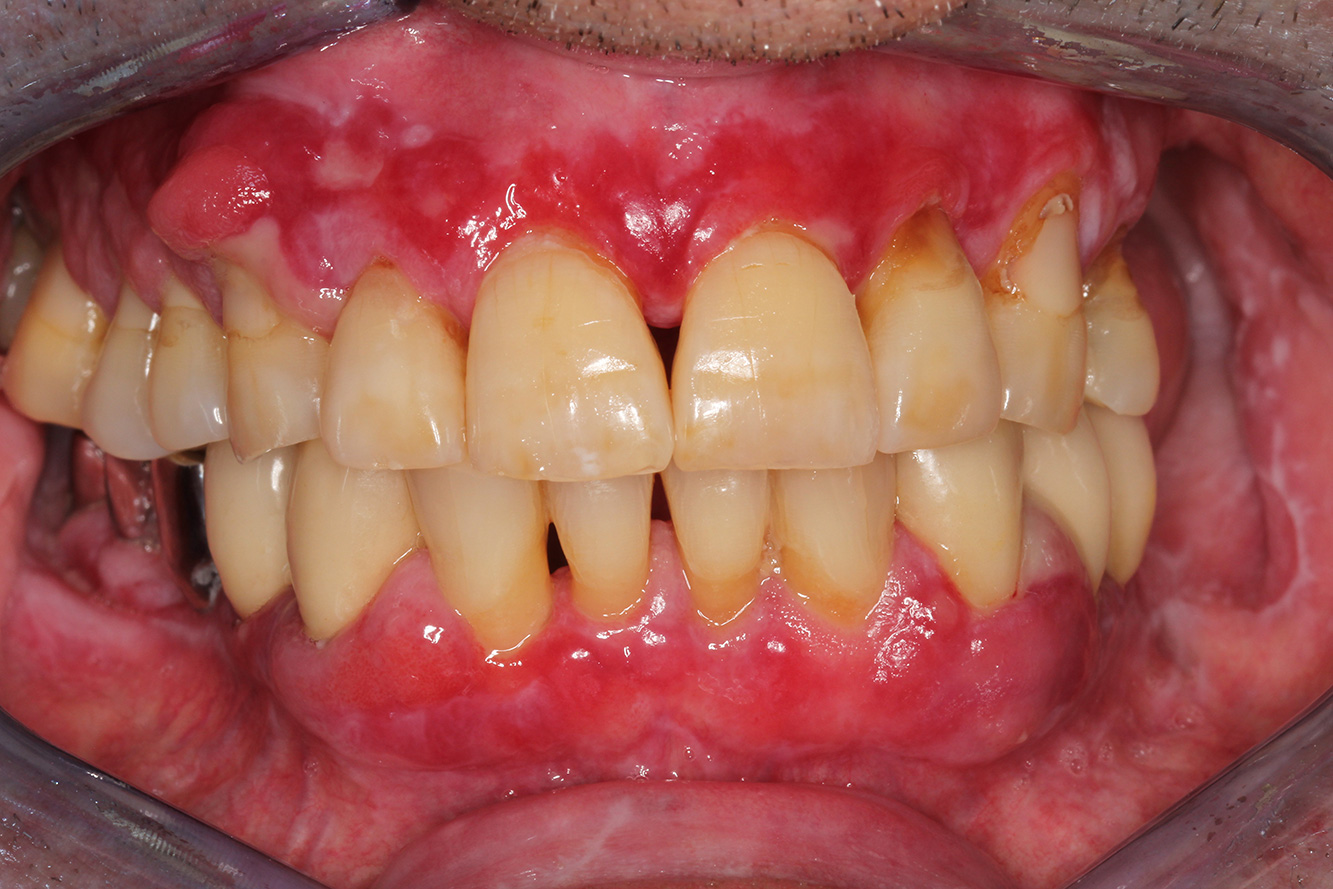

Case presentation: Complex Dental Prosthesis Management

The direct relationship between intraoral and general health, as well as the bidirectional influence that they may have on one another, is well-known (1,2). It is absolutely essential to consider both factors when planning preventive intraoral measures and treatment in the dental practice. The primary objective is the maintenance of patient health and quality of life from both dental and medical perspectives. more